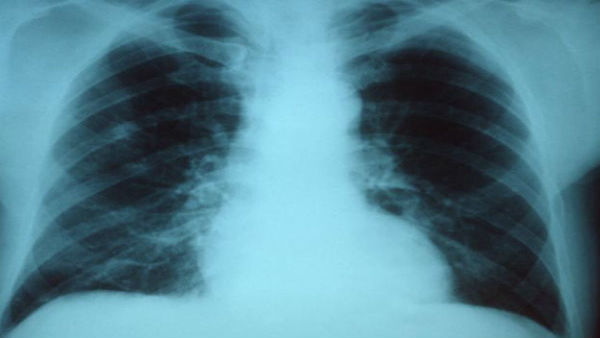

ഐഐടി റൂര്ക്കിയിലെ പ്രൊഫസര് കമല് ജെയിനാണ് പുതി കൊവിഡ് ടെസ്റ്റ് ചെയ്യാനുള്ള സൗകര്യം വികസിപ്പിച്ചെടുത്തത്. കൊറോണ വൈറസ് പരിശോധനയ്ക്ക് വിധേയമാക്കുന്നയാളുടെ എക്സറേയില് നിന്ന് മൂന്ന് മുതല് അഞ്ച് സെക്കന്റുകള്ക്കുള്ളില് വൈറസിനെ കണ്ടെത്താനാകുമെന്നാണ് അദ്ദേഹം വാദിക്കുന്നത്. നിര്മ്മിത ബുദ്ധി ഉപയോഗിച്ചാണ് ഇത് കണ്ടുപിടിക്കുന്നതെന്നും അദ്ദേഹം വാദിക്കുന്നു.

കൊറോണ വൈറസിനെ കണ്ടെത്തുന്നതിനായി നിര്മ്മിത് ബുദ്ധിയെ പരിശീലിപ്പിക്കാന് 60000ല് അധികം നെഞ്ചിന്റെ എക്സറേകള് ഉപയോഗിച്ചെന്ന് കമല് പറയുന്നു. നെഞ്ചിനുള്ളിലെ വിതാനം മനസിലാക്കി നിര്മ്മിത ബുദ്ധി കൊറോണ വൈറസ് ഉണ്ടോ എന്ന് മനസിലാക്കുമെന്നും കമല് വാദിക്കുന്നു. താന് വിശകലനം ചെയ്ത സാമ്പിള് കേസുകളില് സാധാരണ മരണകാരണം കടുത്ത ന്യൂമോണിയയാണ്.

ന്യൂമോണിയ പലതരത്തിലുണ്ട്. മിക്കതരം ന്യമോണിയ രോഗികളെും ആശുപത്രിയില് പ്രവേശിപ്പിച്ചാല് ഭേദമാകും. എന്നാല് കൊവിഡ് മൂലമുണ്ടാകുന്ന ന്യൂമോണിയ കഠിനമാണ്. ശ്വാസകോശത്തെ ചെറിയ ഭാഗത്തിന് പകരം എല്ലാ ഭാഗങ്ങളിലും ഇത് ബാധിക്കുമെന്ന് കമല് പറയുന്നു. ഉഭയകക്ഷി അതാര്യത തിരിച്ചറിയുക, ശ്വാസകോശത്തില് ദ്രാവകം കെട്ടിപ്പടുക്കുന്ന രീതി, ക്ലമ്പുകളുടെ സ്വഭാവം, അതിന്റെ മൊത്തത്തിലുള്ള ക്രമീകരണം എന്നിവയാണ് കൊവിഡിനെ തിരിച്ചറിയാന് സാധിക്കുന്ന പ്രധാനഘടകം. എന്നാല് ഈ ഡോക്ടര്മാര്ക്ക് സമയവും പരിചയ സമ്പത്തും ആവശ്യമാണ്. തങ്ങളുടെ നിര്മ്മിത ബുദ്ധി ആപ്ലിക്കേഷനുപയോഗിച്ച് പാറ്റേണുകളെ സമയബന്ധിതമായി തരംതിരിക്കാന് കഴിയുമെന്നും കമല് അവകാശപ്പെടുന്നു.